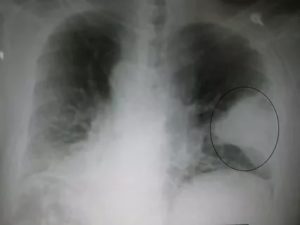

- Абсцедирующая пневмония. Проявляется обширным затемнением пораженной области, признаками утолщения плевры и наличием полостей разного размера, наполненных жидкостью.

Казеозная пневмония развивается под влиянием туберкулёзной инфекции.

Эта форма заболевания характеризуется:

- наличием участков инфильтрации (уплотнения);

- образованием полостей;

- появлением неровных пустот.

Это позволяет дать точное определение диагнозу, уточнить тип пневмоцисты.

Осложнениями называют разные формы абсцессов и плевритов, а также перисциссурит, которые проявляются на рентгеновских снимках.

Также при абсцедирующей форме пневмонии на рентгене могут отображаться распады тканей лёгких (они сливаются между собой).

Заметить плеврит на снимке можно:

- по затемнению полей лёгких (за счёт обилия внутренней жидкости);

- по смещению средостения.

Воспаление плевры обозначено чёткими контурами щели между долями, расширенным лёгочным корнем ближе к очагу поражения.

Сравнение здоровых и воспаленных легких на рентгенографии Абсцесс лёгких на рентгеновском снимке Абсцесс при левостороннем верхнедолевом воспалении лёгких Очаговая пневмония Крупозная пневмония на рентгене Казеозная пневмония